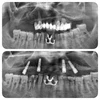

Implant Treatment